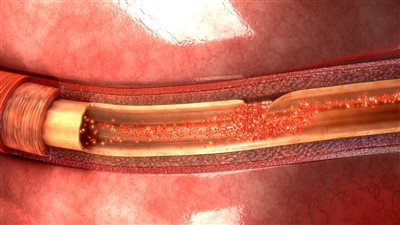

ولمن يرغب في معرفة إجاية سؤال ما هو إنسلاخ الشريان الأورطي؟، يوضح أخصائي أمراص الباطنة والقلب والصدر، أن انسلاخ الشريان الأورطى يعد من الحالات الطبية الخطيرة والتي تصيب الطبقات الداخلية للشريان؛ حيث تنسلخ تنفصل الطبقة الداخلية عن الطبقة الوسطى للشريان؛ نتجو تراكم الدم بينهما، منبهًا إلى قد يسبب الوفاة في حال انفجر الشريان.